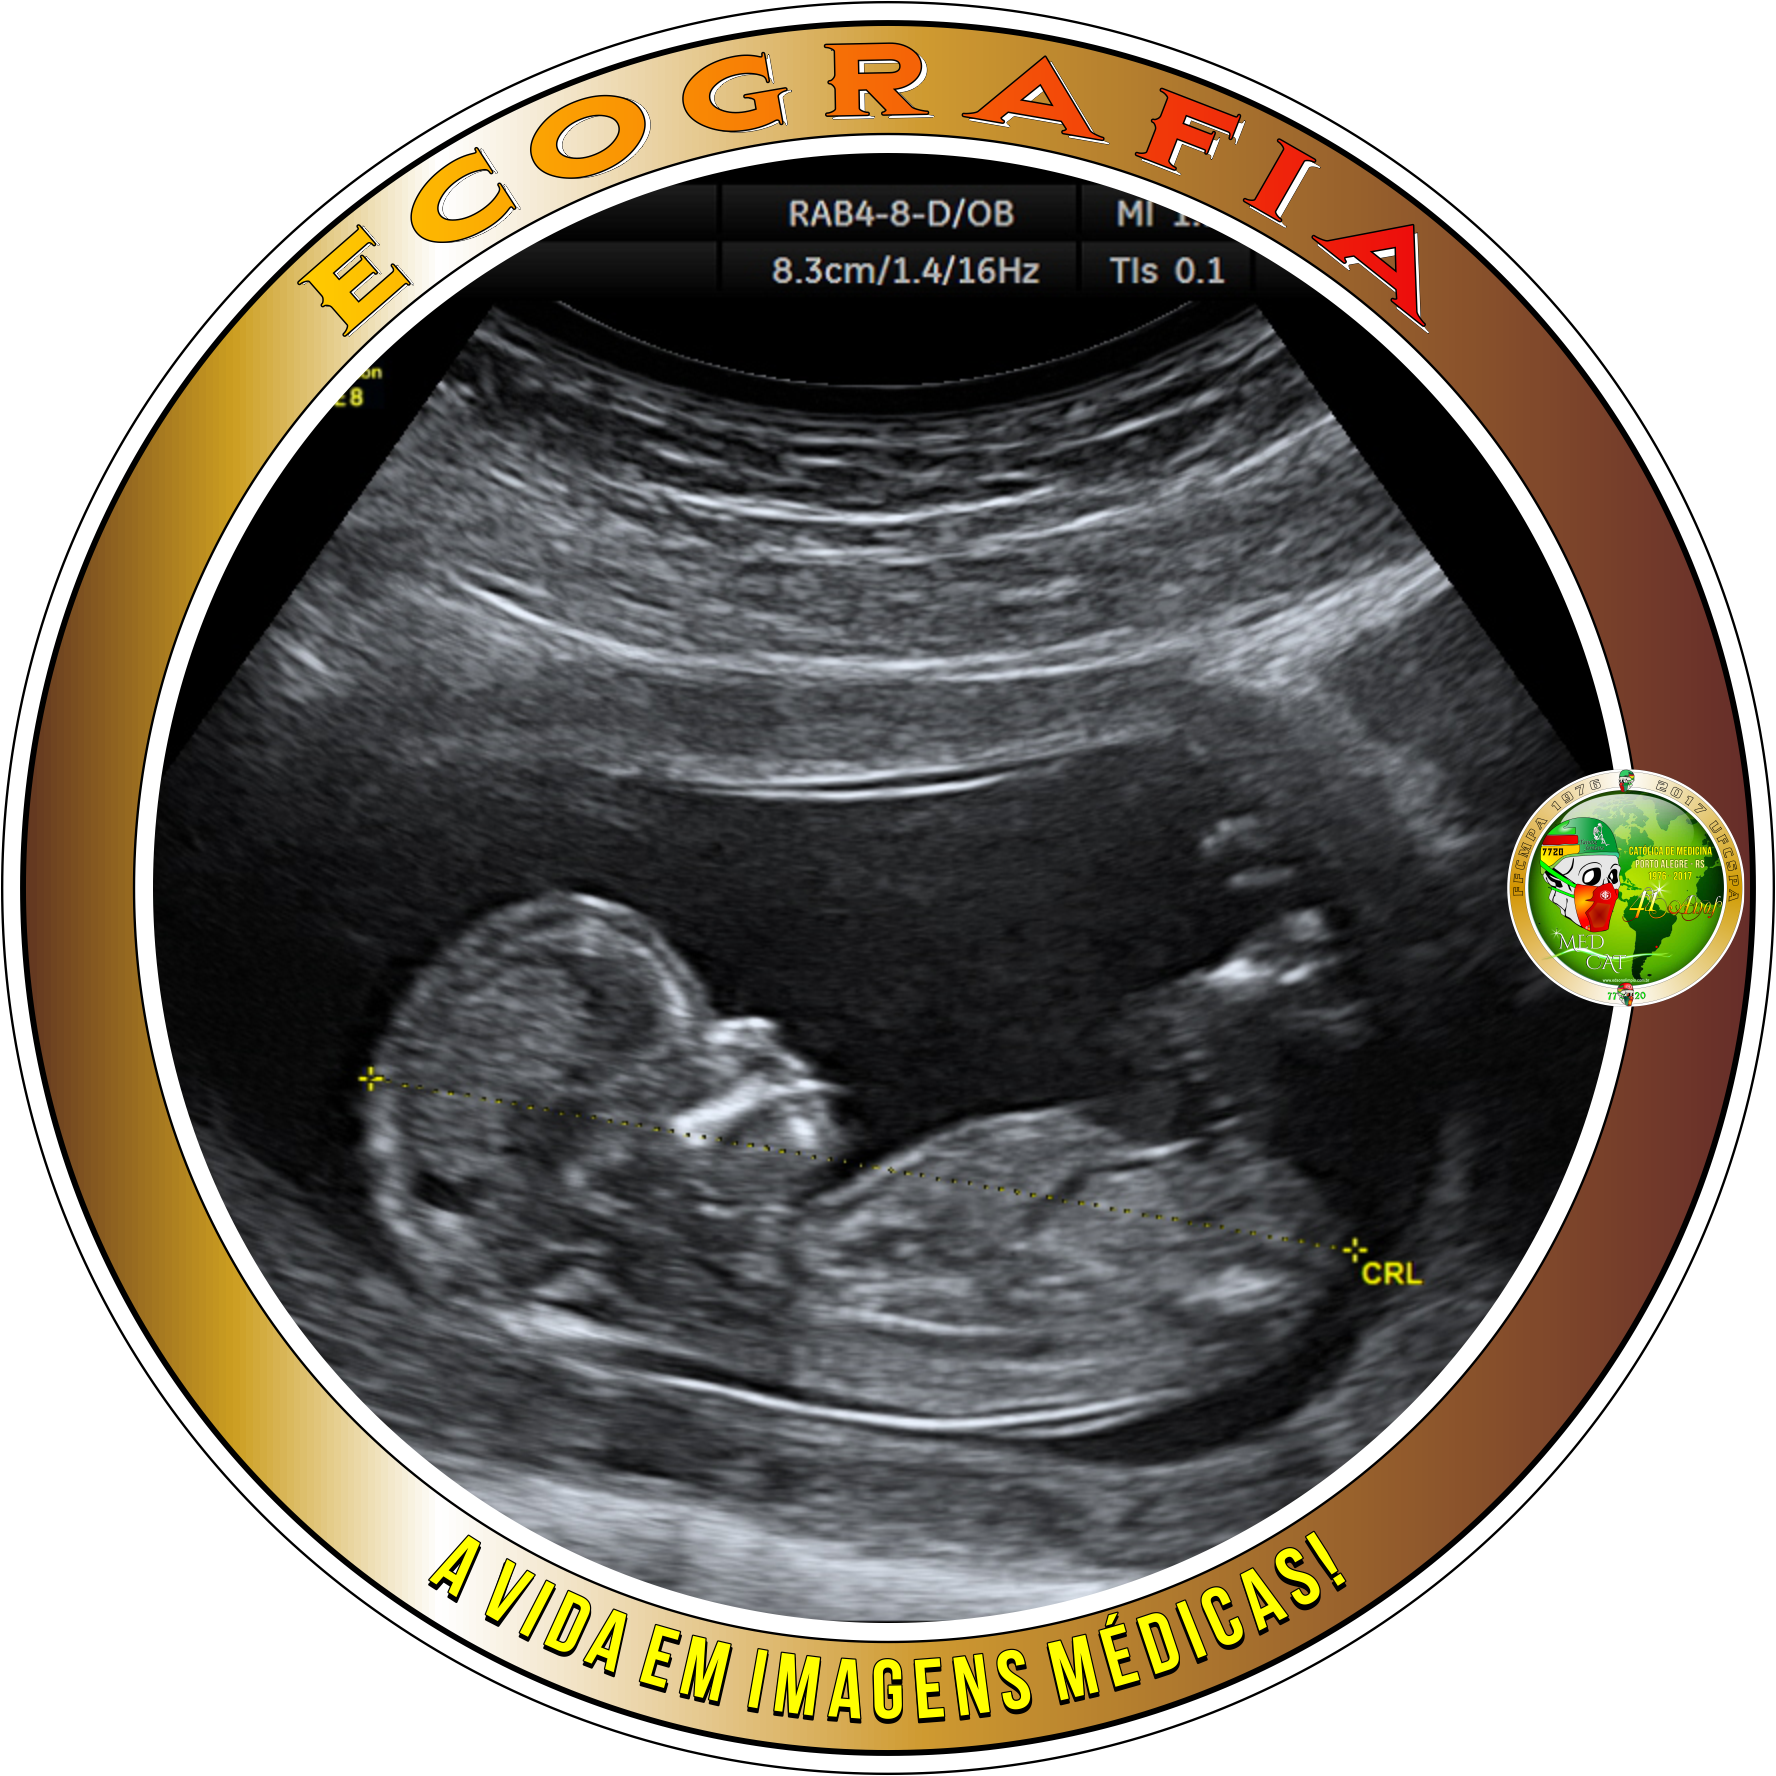

Ecografia * Medicina * Especialidades Médicas